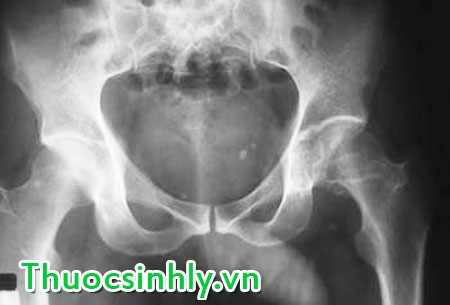

Giảm mật độ khoáng xương: Xương là một khối lượng rắn chắc không có mỡ trong cơ thể con người, một chủ thể nhận cảm tác dụng của nội tiết tố tình dục nói chung và của Testosterone nói riêng. Testosterone tăng trưởng giúp cho sự gắn kết chắc chắn giữa thân xương và màng xương để rồi phát triển đồng bộ lớn và độ dài của xương.

Testosterone cũng giúp cho sự phát triển kết cấu của xương do mật độ tinh thể calcium tăng trưởng. Tuổi già và sự giảm sút nồng độ Testosterone trong máu dễ gây bệnh loãng xương và dễ bị gẫy xương lớn do những nguyên nhân đơn giản.